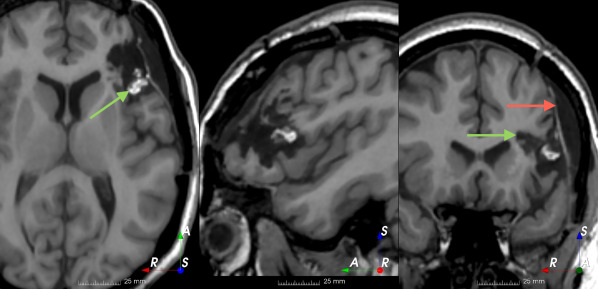

Refer to caption

(a)

(b)

(c)

(d)

(e)

(f)

(g)

(h)

Figure 6: Examples of challenging images for cavity segmentation. (a) Small frontal lesionectomy surrounded by hypointense white matter (b) Brain shift after contralateral temporal lobectomy (not shown) (c) Small frontal lesionectomy near the Sylvian fissure (d) Lack of boundaries between oedema and resection cavity (e) Possible blood clot within the cavity (f) Brain shift, oedema and resection cavity (g) Arachnoid cyst and resection cavity (h) Cerebellar degeneration. Green annotations represent areas that correspond to resection cavities; red annotations represent areas that do not.